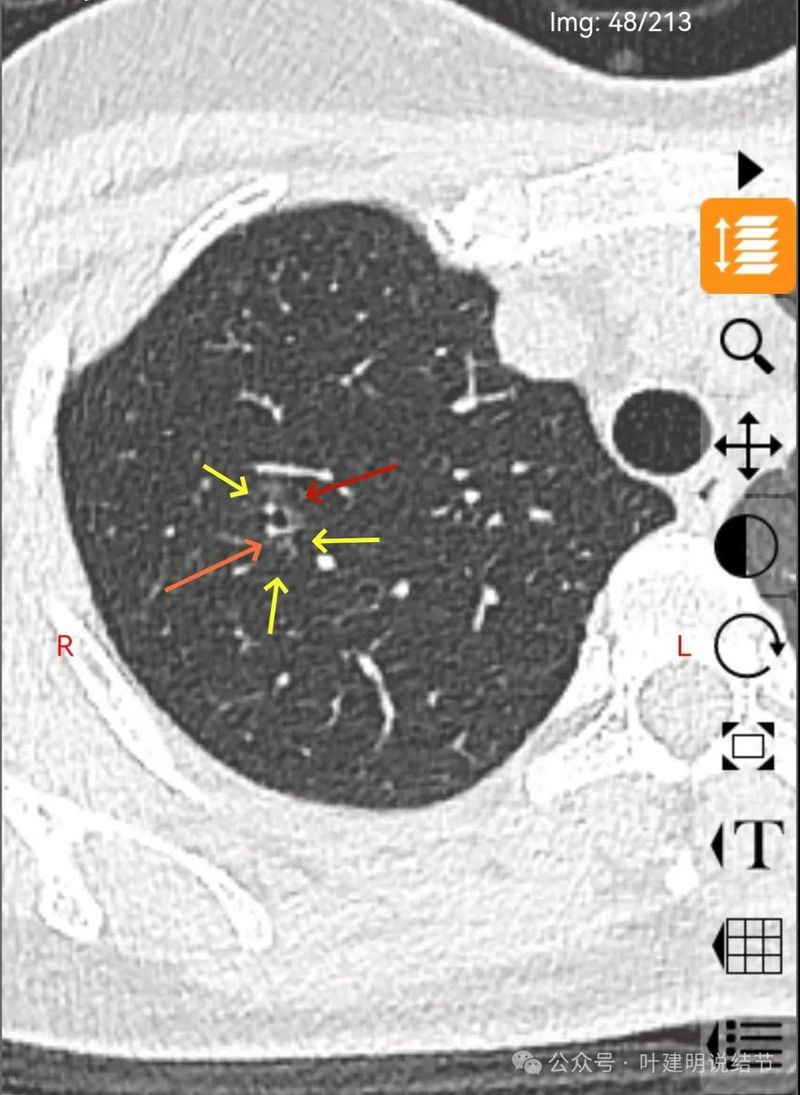

表面不平,分叶明显,灶边有小空泡征,灶边另有多处血管贴边,也见血管分支进入。

病灶密度稍不均,分叶明显,中间有扩张的细支气管,血管有贴边。整体轮廓与瘤肺边界清。

有实性成分出现。

混合密度,月牙铲征,轮廓清,血管多支进入,灶内实性成分明显,表面不平分叶,灶内细支气管扩张。